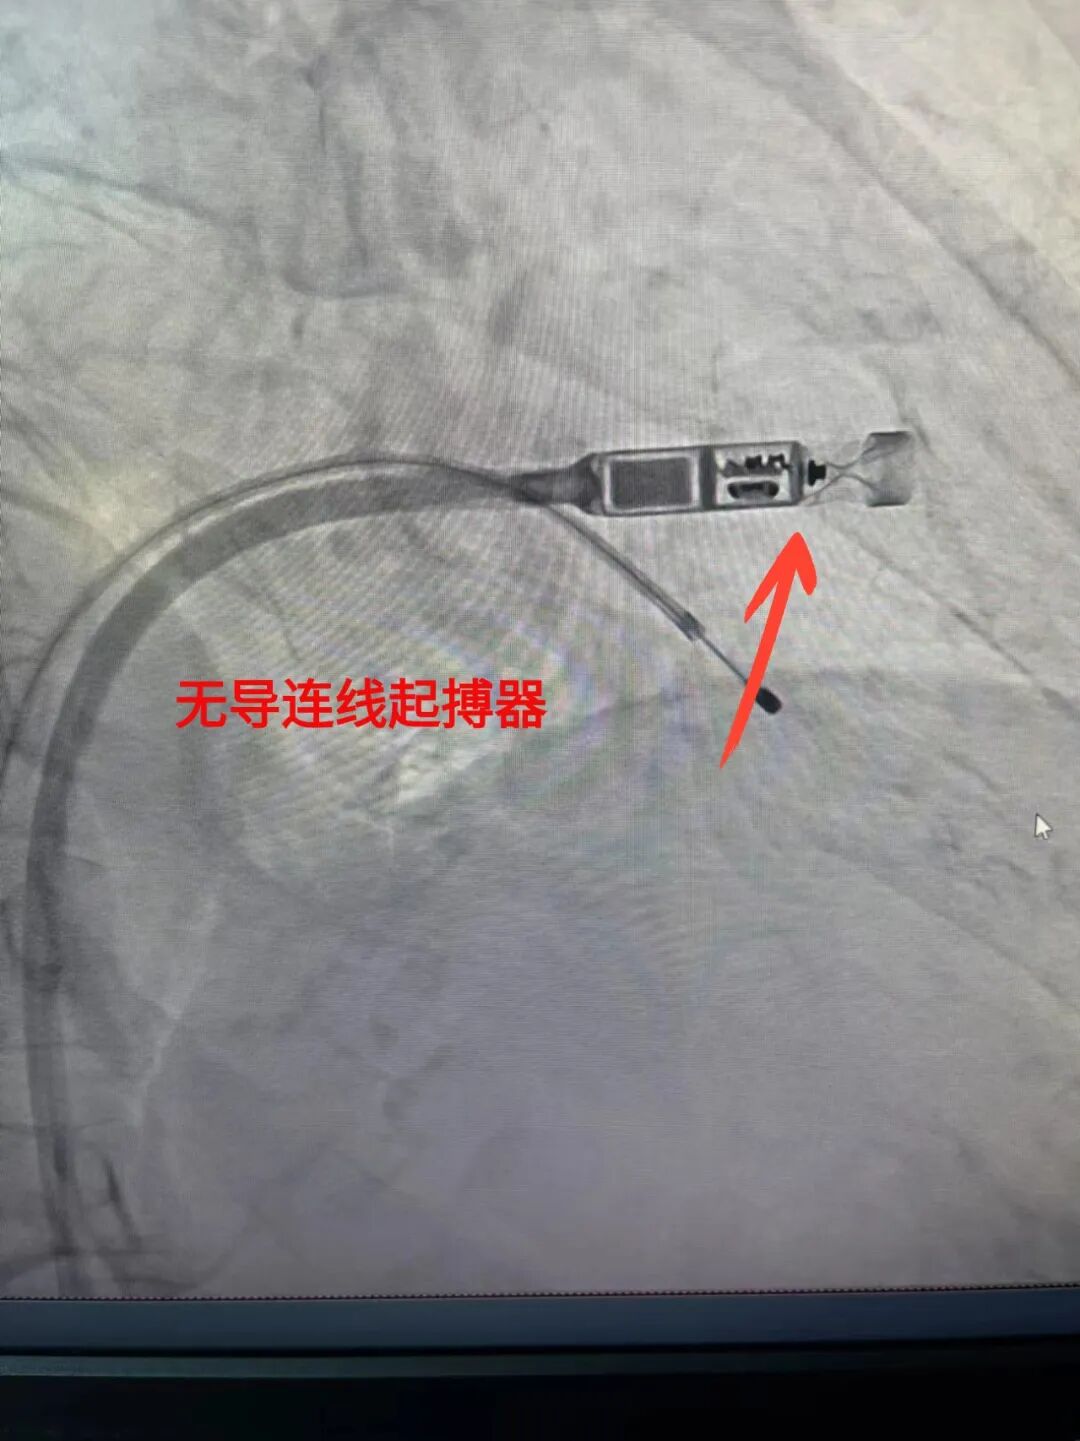

无导线起搏术:引领心脏起搏新纪元

作为心脏节律管理领域的重大突破,无导线起搏术在我院的成功应用,标志着心脏起搏器技术迈入了全新的无线时代。该手术无需植入传统导线,体积小巧,兼容性好,为患者提供了更加舒适、安全的治疗选择,展现了中心在心脏电生理领域的创新实力。